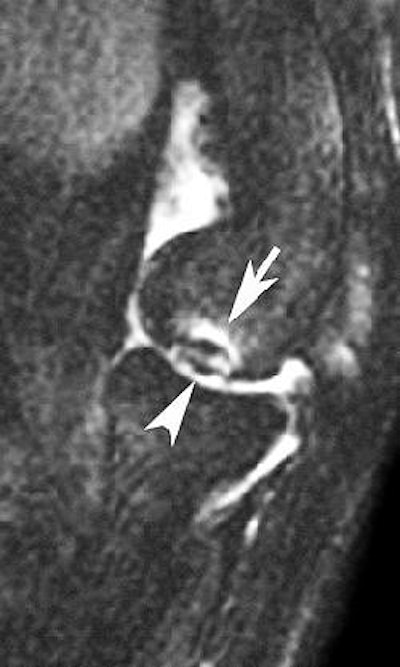

| Sagittal MRI of JOCD on 1.5-tesla scanner. Protocol included FSE and T2-weighted imaging (TR/TE 3500/55). Image courtesy of Dr. Nancy Major, Duke University Medical Center, Durham, NC. |

"You should see all of this with a standard knee protocol," that includes "a cartilage-sensitive sequence and a fluid-sensitive sequence," she said. "To help determine if the OCD is going to be stable or unstable, we're looking for fluid encircling that fragment."

"MRI is king (for JOCD)," agreed Beall. "If there's a joint effusion, you need the ability to see the fluid surrounding the fragment or going into the fragment. If there's not a whole lot of joint fluid there, which is atypical, we do an MR arthrogram."

Dr. Valmai Cook, a radiologist at Queen Mary's Hospital for Children in Carshalton, U.K., shared her preferred MR protocol for assessing JOCD: "T2 SE sequences with fat suppression can distinguish hyaline cartilage from synovial fluid and can demonstrate a flap or tear in the cartilage, which indicates an unstable lesion that will need surgery. This can usually only be demonstrated if there is an effusion present. Adverse features on MRI are size (> 2 cm), location (weight-bearing surface), narrow growth plates suggesting maturity, and an effusion. The latter is also an adverse clinical feature."